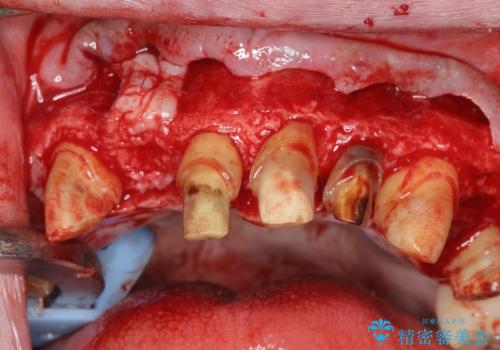

セラミック治療を行う前に歯周病の問題を解決すべく歯周外科を行い歯周ポケットを除去し整備したのちセラミックブリッジ・クラウンの製作を行います。

歯周外科を行ったことで非常に安定した歯周環境となり、引き締まった歯ぐきとなりました。